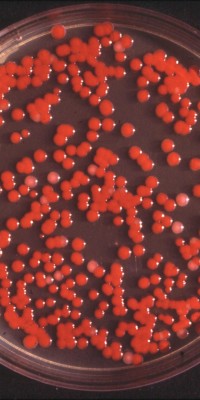

Раздел: Другие животные